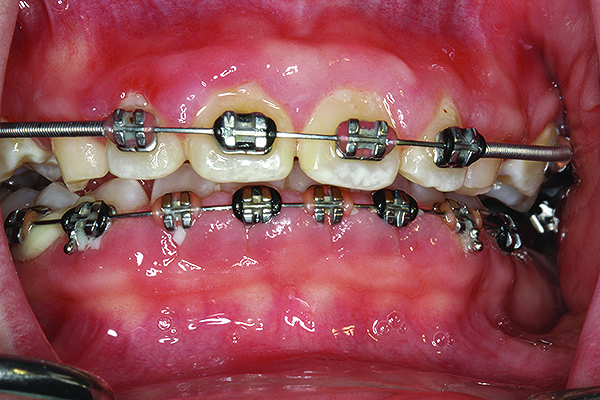

Fig 8. Case 1 clinical photograph of No. 19 after root canal treatment and crown fabrication.

Figure 8

Evaluation of the patient’s full mouth series of radiographs revealed signs of mild periodontal bone loss and a large carious lesion/defective restoration on tooth No. 19. A treatment plan was devised that included oral hygiene instructions, scaling/root planing, root canal treatment on No. 19, crown fabrication on No. 19, and re-evaluation 4 to 6 weeks later. During the re-evaluation appointment, oral hygiene was shown to be slightly improved, and a 3-month periodontal maintenance interval was suggested (Figure 8). The patient reported a significantly decreased degree of malodor and was very satisfied.